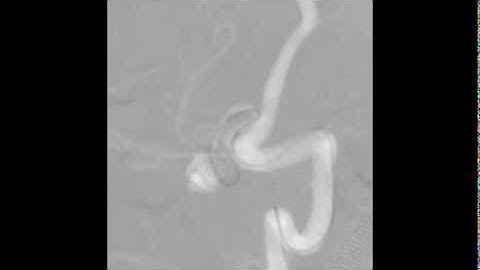

3D nnU-Net with Multi Loss Ensembles for Automated Segmentation of Intracranial Aneurysm